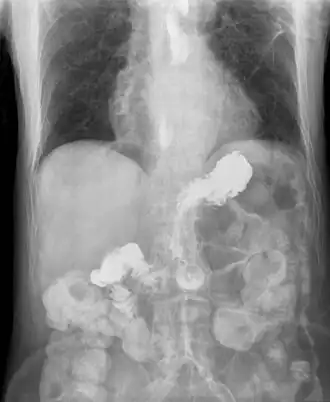

Le transit œsophagien consiste à faire avaler au patient une pâte radio-opaque et de suivre sa progression dans le tube digestif. Cet examen permet de visualiser certaines complications (rétrécissements) ou certains terrains favorisants (hernie hiatale).